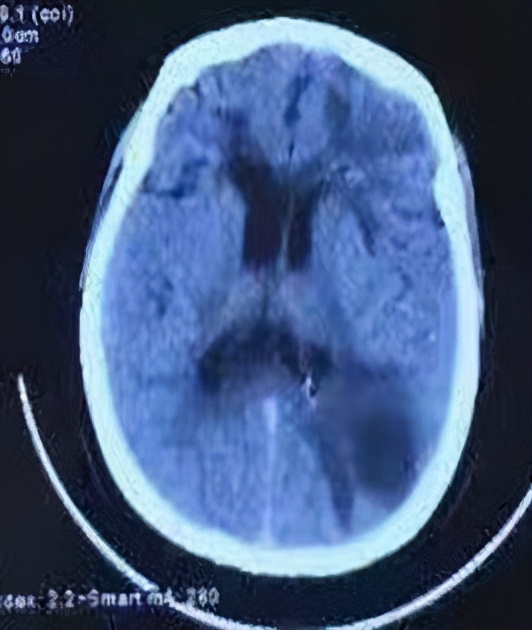

利用院内先进的512排CT对脑脓肿病灶进行三维立体定位,选择最佳穿刺部位,多次进行术前模拟训练,并制定风险预案。一切准备就绪后,在日间手术室局部麻醉下进行微创穿刺脓肿引流术(图3)。因为术前准备充分,手术很顺利,仅用60分钟完成,手术穿刺针进入脑内约50mm,引流出浑浊脓液25ml(图4),用生理盐水缓慢冲洗置换出微浊液体300ml。术后患者恢复良好,无肢体麻木无力等神经功能损害,头部CT复查提示手术治疗脓肿病灶脓液引流非常干净,脓肿病灶完全消失,小脓肿病灶经抗炎治疗,病灶缩小(图2)。

图2